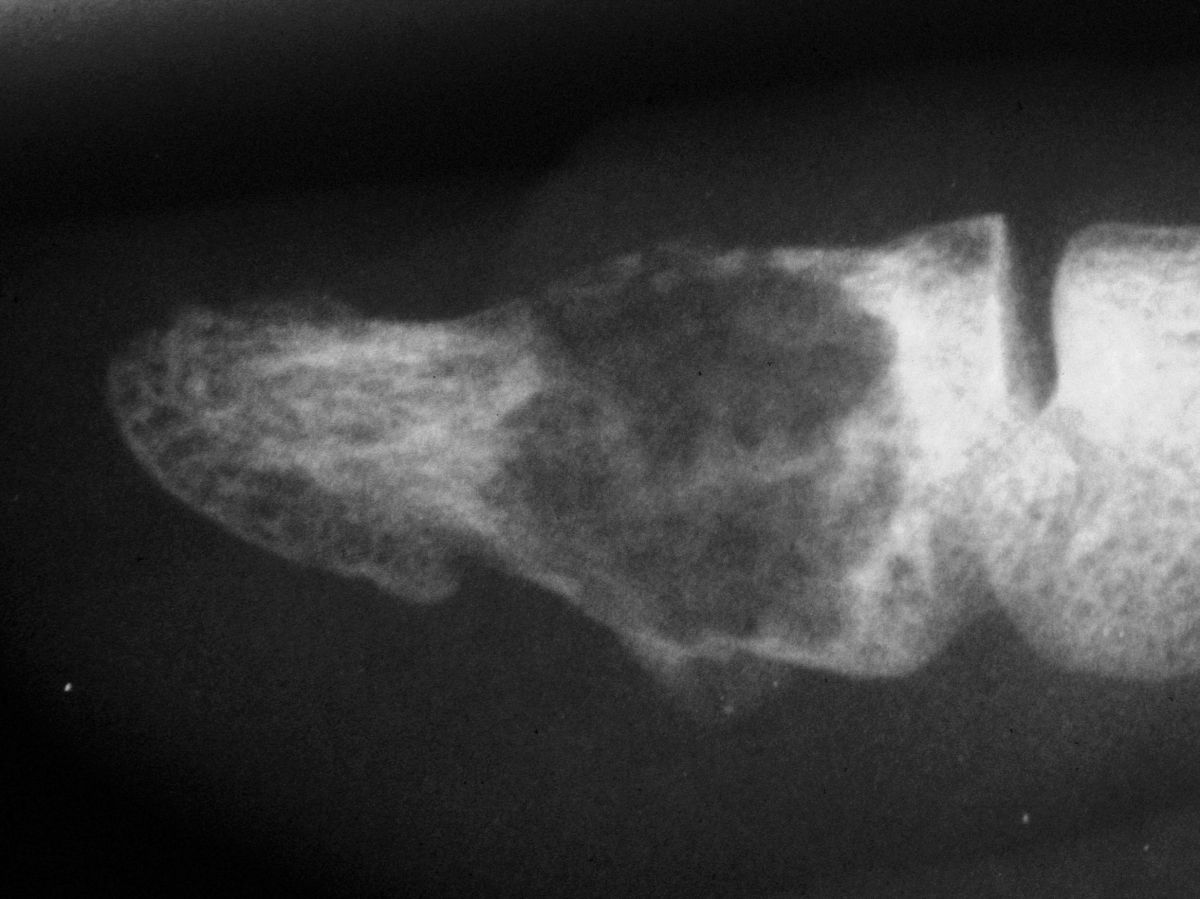

| Case 2. This patient presented months after having "injured" her middle fingertip, feeling that the finger was not normal. Xrays were consistent with an enchondroma and probable dorsal angulation from a healed pathologic fracture. |